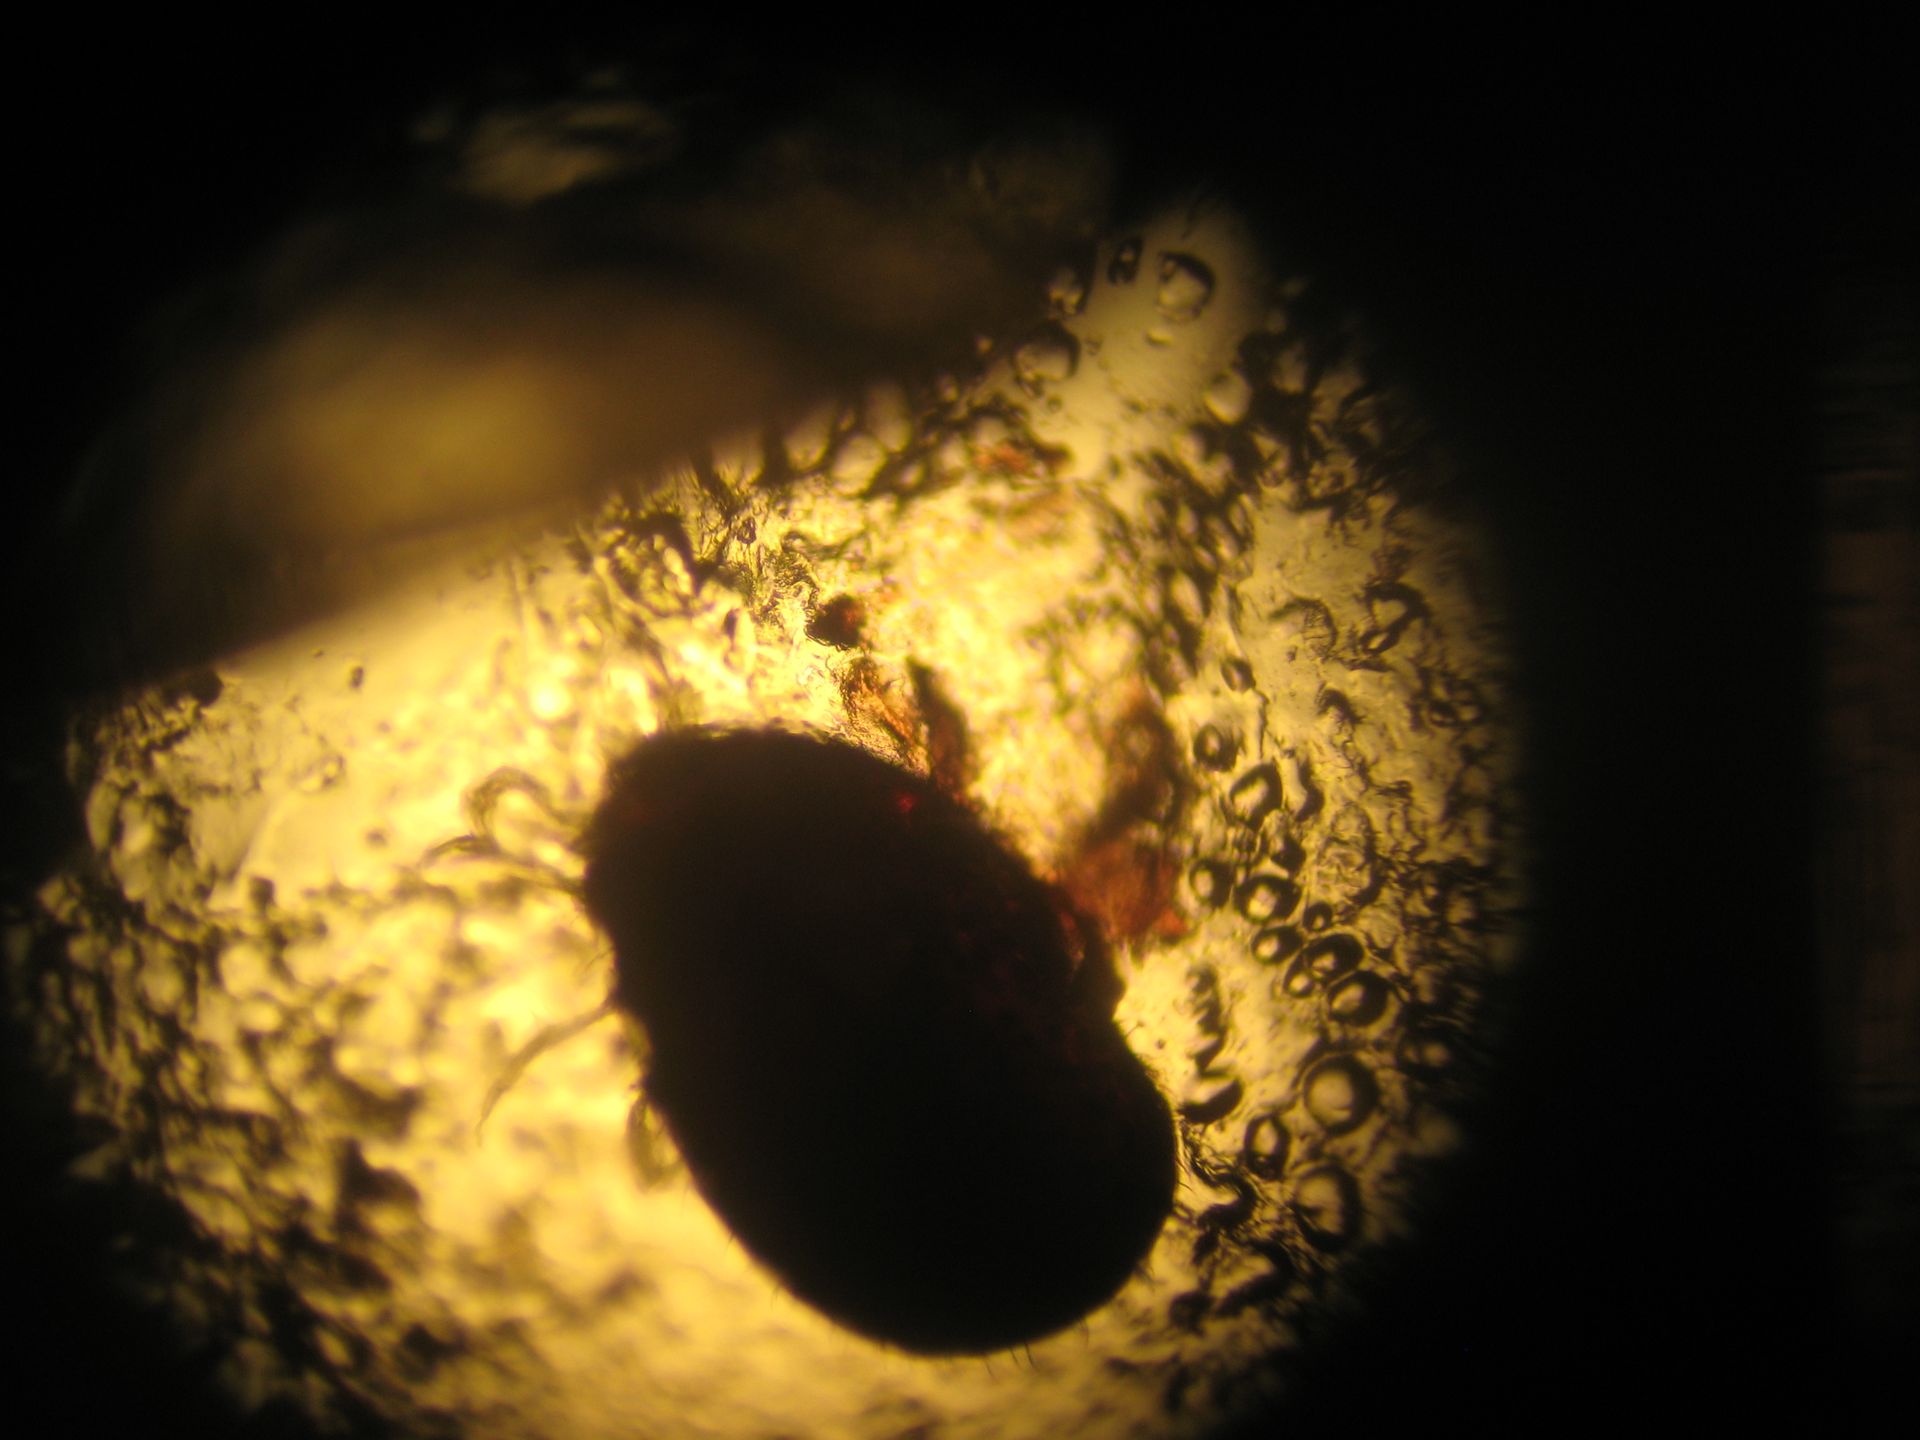

Ophyonissus natricis - Acarien

Ophionyssus natricis est un acarien des serpents et des lézards qui est très fréquent en terrariophilie. Le parasite vit dans les supports et le substrat et vient infecter le serpent. On le retrouve particulièrement autours des yeux. Chez les serpents, on pense qu'il peut transmettre certaines maladies dont l'IBD (infectious body disease).

Dans tous les cas, il provoque des troubles de mues et des démangeaisons. Son traitement passe par des antiparasitaires et aussi une désinfection de l'environnement.